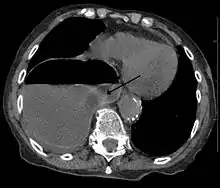

A right sided diaphragmatic hernia with the stomach in the chest (left side of image marked by the arrow). Note the air fluid level in the stomach.

Diagnosis can be made by either CT or X-ray.